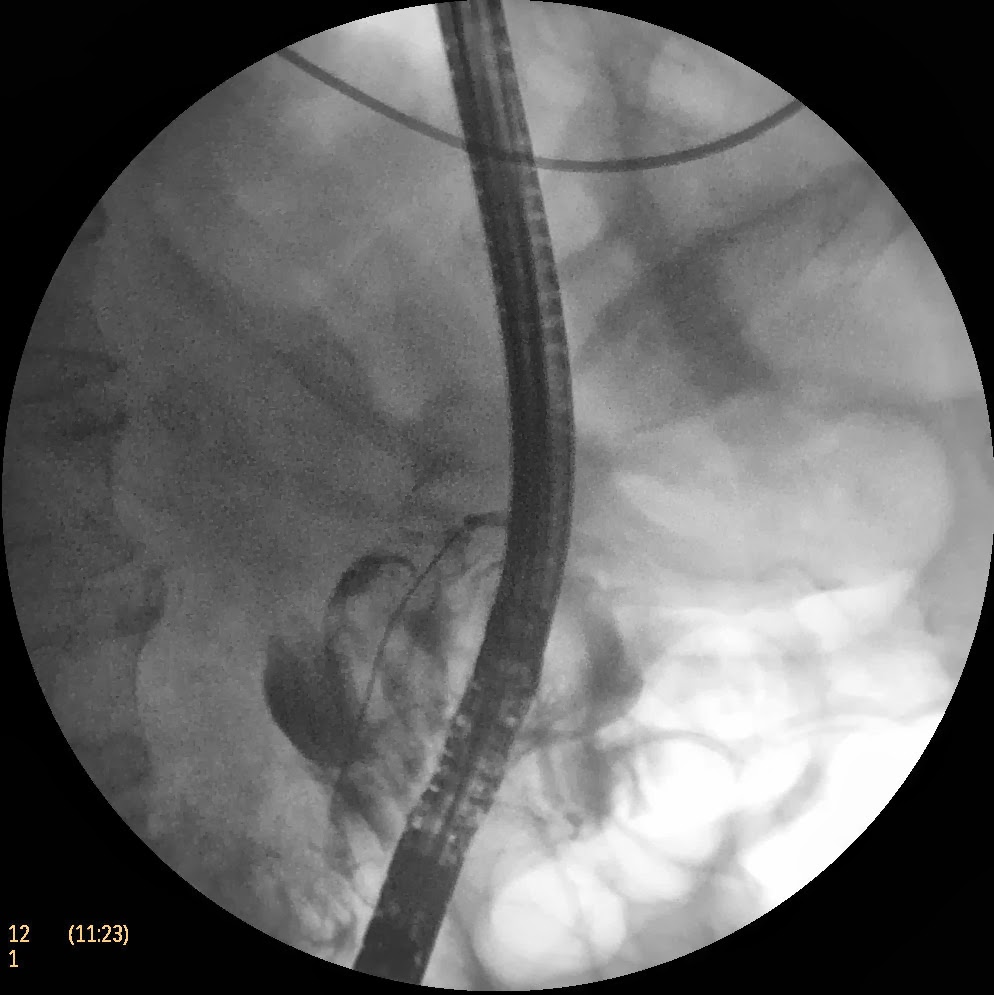

Paciente varón de 62 años de edad con antecedentes de EPOC, HTA e hiperuricemia. Consulta en nuestro centro por un cuadro de dolor abdominal alto de > 2 meses de duración junto a anorexia y pérdida de hasta 10 Kgr en los últimos 3 meses. De forma paulatina fue recuperando peso y las molestias disminuyeron considerablemente. Analíticamente solo destacaba una GGT de 110 UI/L con marcadores tumorales (adenocarcinoma) normales. Se practicó una ecografía abdominal donde se apreciaba un masa intracoledociana (nivel medio y distal) que provocaba una gran dilatación de la vía biliar extrahepática (> 20 mm) y dilatación retrógrada leve de la vía biliar intrahepática. La vesícula biliar estaba colapsada con litiasis en su inetrior. El diagnóstico diferencial ecográfico se planteaba entre molde de barro biliar vs colangiocarcinoma polipoideo. Se realizó CPRE con la extracción de una gran cantidad de material biliar que corroboró el diagnóstico benigno del proceso.

Se expone este caso por la gran variabilidad en la que los problemas clínicos se presentan en la medicina y la CPRE no iba a ser menos. Es llamativo como se puede ver en el video, la enorme cantidad de barro biliar que se extrae.